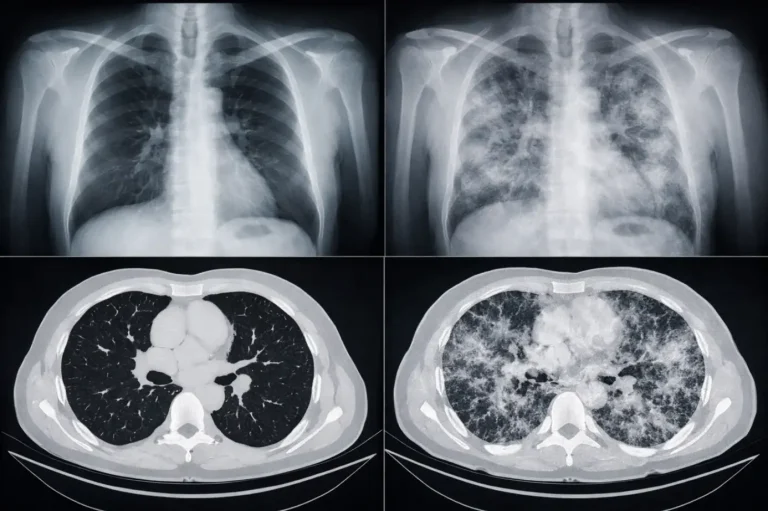

Пневмония остаётся одной из самых частых причин ухудшения дыхания и обращения к врачу, особенно в сезоны простуд и вирусных вспышек. Главная сложность…

Медицинские снимки — это один из главных источников информации для врача, когда нужно быстро понять, что происходит внутри организма. Но даже качественное…

ИИ в диагностике на основе КТ и МРТ всё чаще становится тем инструментом, который помогает врачу увидеть то, что человеческий глаз может…